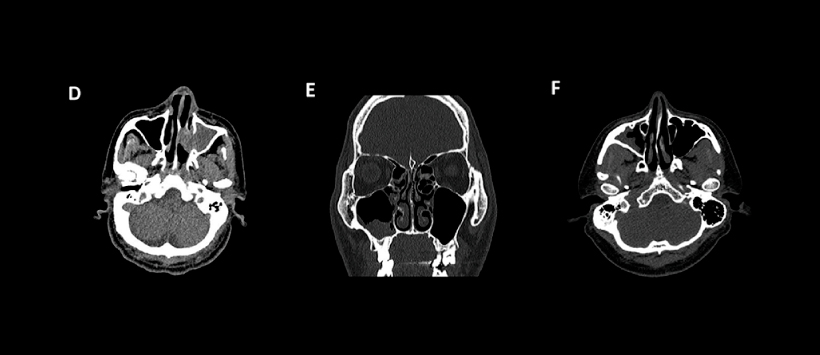

Figura D, corte axial de TC que muestra opacificación del seno maxilar derecho con erosión de la pared medial.

Figura E, corte coronal de TC que muestra engrosamiento irregular de la mucosa en el seno maxilar derecho con esclerosis de la pared anterior.

Figura F, corte coronal de TC que muestra engrosamiento irregular de la mucosa sinusal en el lado derecho.